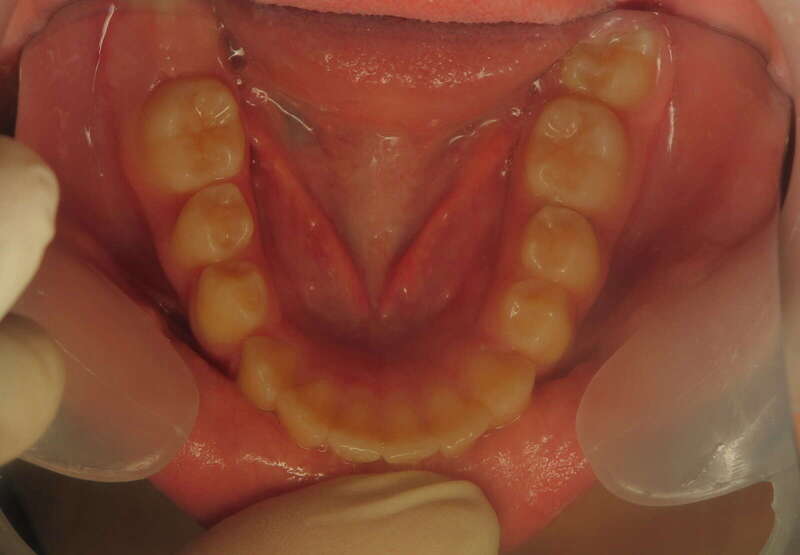

Cas n°1 d'orthodontie chirurgicale par aligneurs - adulte

Voici l'analyse de ce cas clinique concernant un patient adulte de 30 ans, illustrant la réussite d'un protocole ortho-chirurgical mené avec des aligneurs. Ce cas met en lumière l'importance de la fonction musculaire et respiratoire au-delà de l'alignement dentaire.

À 30 ans, la croissance est terminée, ce qui rend la correction d'un décalage osseux uniquement possible par la chirurgie :

• Rétrognathie Mandibulaire (Profil Rétrusif) : Le patient présentait un menton fuyant, caractéristique d'une mandibule trop courte ou positionnée trop en arrière.

• Déficit Fonctionnel : L'absence d'engrènement correct entraînait une mastication inefficace. Le patient rapportait une sensation de "manque de force" lors de l'alimentation.

• Supraclusion et Décalage : Un recouvrement incisif important qui bloquait toute dynamique mandibulaire saine.

• Usure et Fatigue : Chez l'adulte, ces malpositions entraînent souvent des tensions musculaires et une usure prématurée du capital dentaire.Le traitement a combiné la précision numérique des aligneurs et la puissance de la chirurgie maxillo-faciale :

1. Préparation par Aligneurs : Les arcades ont été préparées (alignement et coordination) pour que, une fois la mâchoire avancée par le chirurgien, les dents s'emboîtent immédiatement.

2. Avancée Mandibulaire Chirurgicale : Le repositionnement osseux a permis de corriger le profil de manière spectaculaire, redonnant de la force et de la structure au bas du visage.

3. Réhabilitation de la Force Masticatrice : C'est le point clé du ressenti patient. En retrouvant un engrènement de Classe I, les muscles masticateurs travaillent enfin avec un rendement optimal. Le patient ressent physiquement ce retour de puissance musculaire.

4. Harmonie du Profil : L'avancée du menton a équilibré les proportions du visage, offrant un profil plus affirmé et une meilleure définition de la ligne mandibulaire.